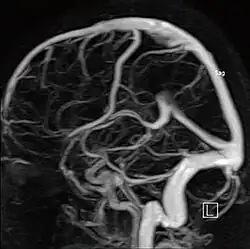

МР-ангиография

Артерии головного мозга

Магнитно-резонансная ангиография (МР-ангиография, МРА) — метод получения изображения кровеносных сосудов при помощи магнитно-резонансного томографа. Исследование проводится на томографах с напряжённостью магнитного поля не менее 0.3 Тл. Метод позволяет оценивать как анатомические, так и функциональные особенности кровотока.

Ангиография артерий головного мозга (времяпролётная ангиография)